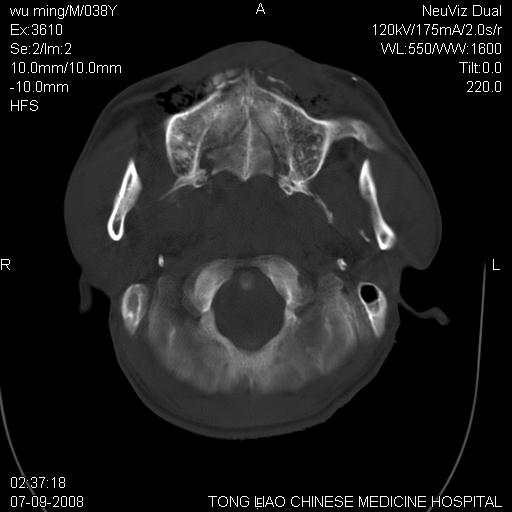

标题: CT14544:患者5楼坠下15分钟后CT扫描,2小时后死亡,请战友指 [打印本页]

标题: CT14544:患者5楼坠下15分钟后CT扫描,2小时后死亡,请战友指

颅底多发骨折.上颌骨多发骨折

右侧眼眶,上颌骨,鼻骨、上颌窦等很多

考虑:面骨、颅底骨多发骨折,颅内高压(脑肿胀)。

1)颅底骨及颌面骨多发性骨折。2)副鼻窦及双侧鼻腔积血。

考虑:面骨、颅底骨多发骨折

前颅窝颅底骨折,死的原因应该从头部来看不用说就是重度颅脑损伤。

颅底、上颌骨,双侧颧骨多发骨折。死因或许与此无关,是否有腹部脏器损伤有关

考虑:面骨、颅底骨多发骨折。从五楼摔下还伤着头了,不死才怪;估计有弥漫性轴索损伤。